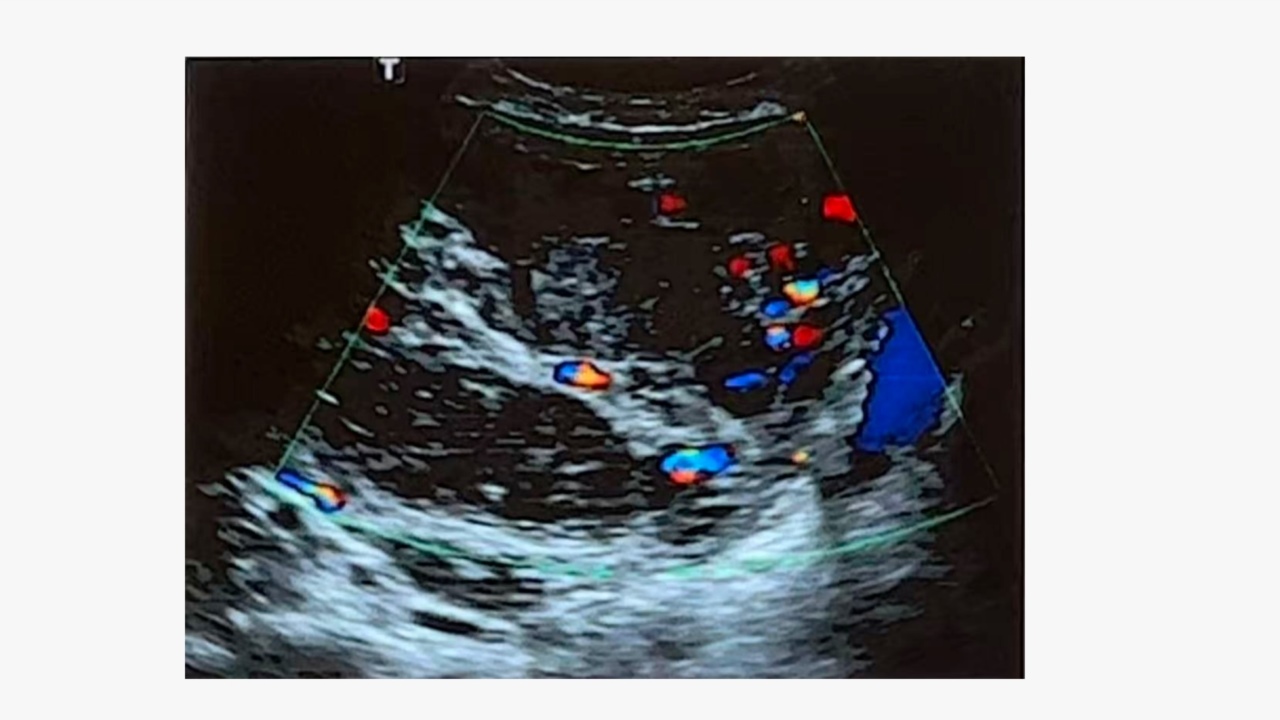

盆腔超声:往往显示子宫明显增大、形状不规则、多个肌瘤结节,宫旁血流信号丰富,盆腔静脉往往显示不清。